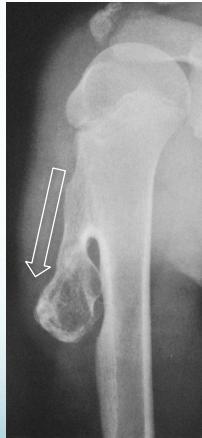

Osteochondroma (Exostosis)

- A common lesion

- Ends of long bone

- Bony overgrowth:

- Away from epiph. plate

- Covered by cartilage

- Growth:

- Stops when epiphysis close

- If continues later:

- ? Malignant transformation

Source: radiopaedia.org, Apley’s System of Orthop. And Fractures

Complications

- May fracture: becomes painful